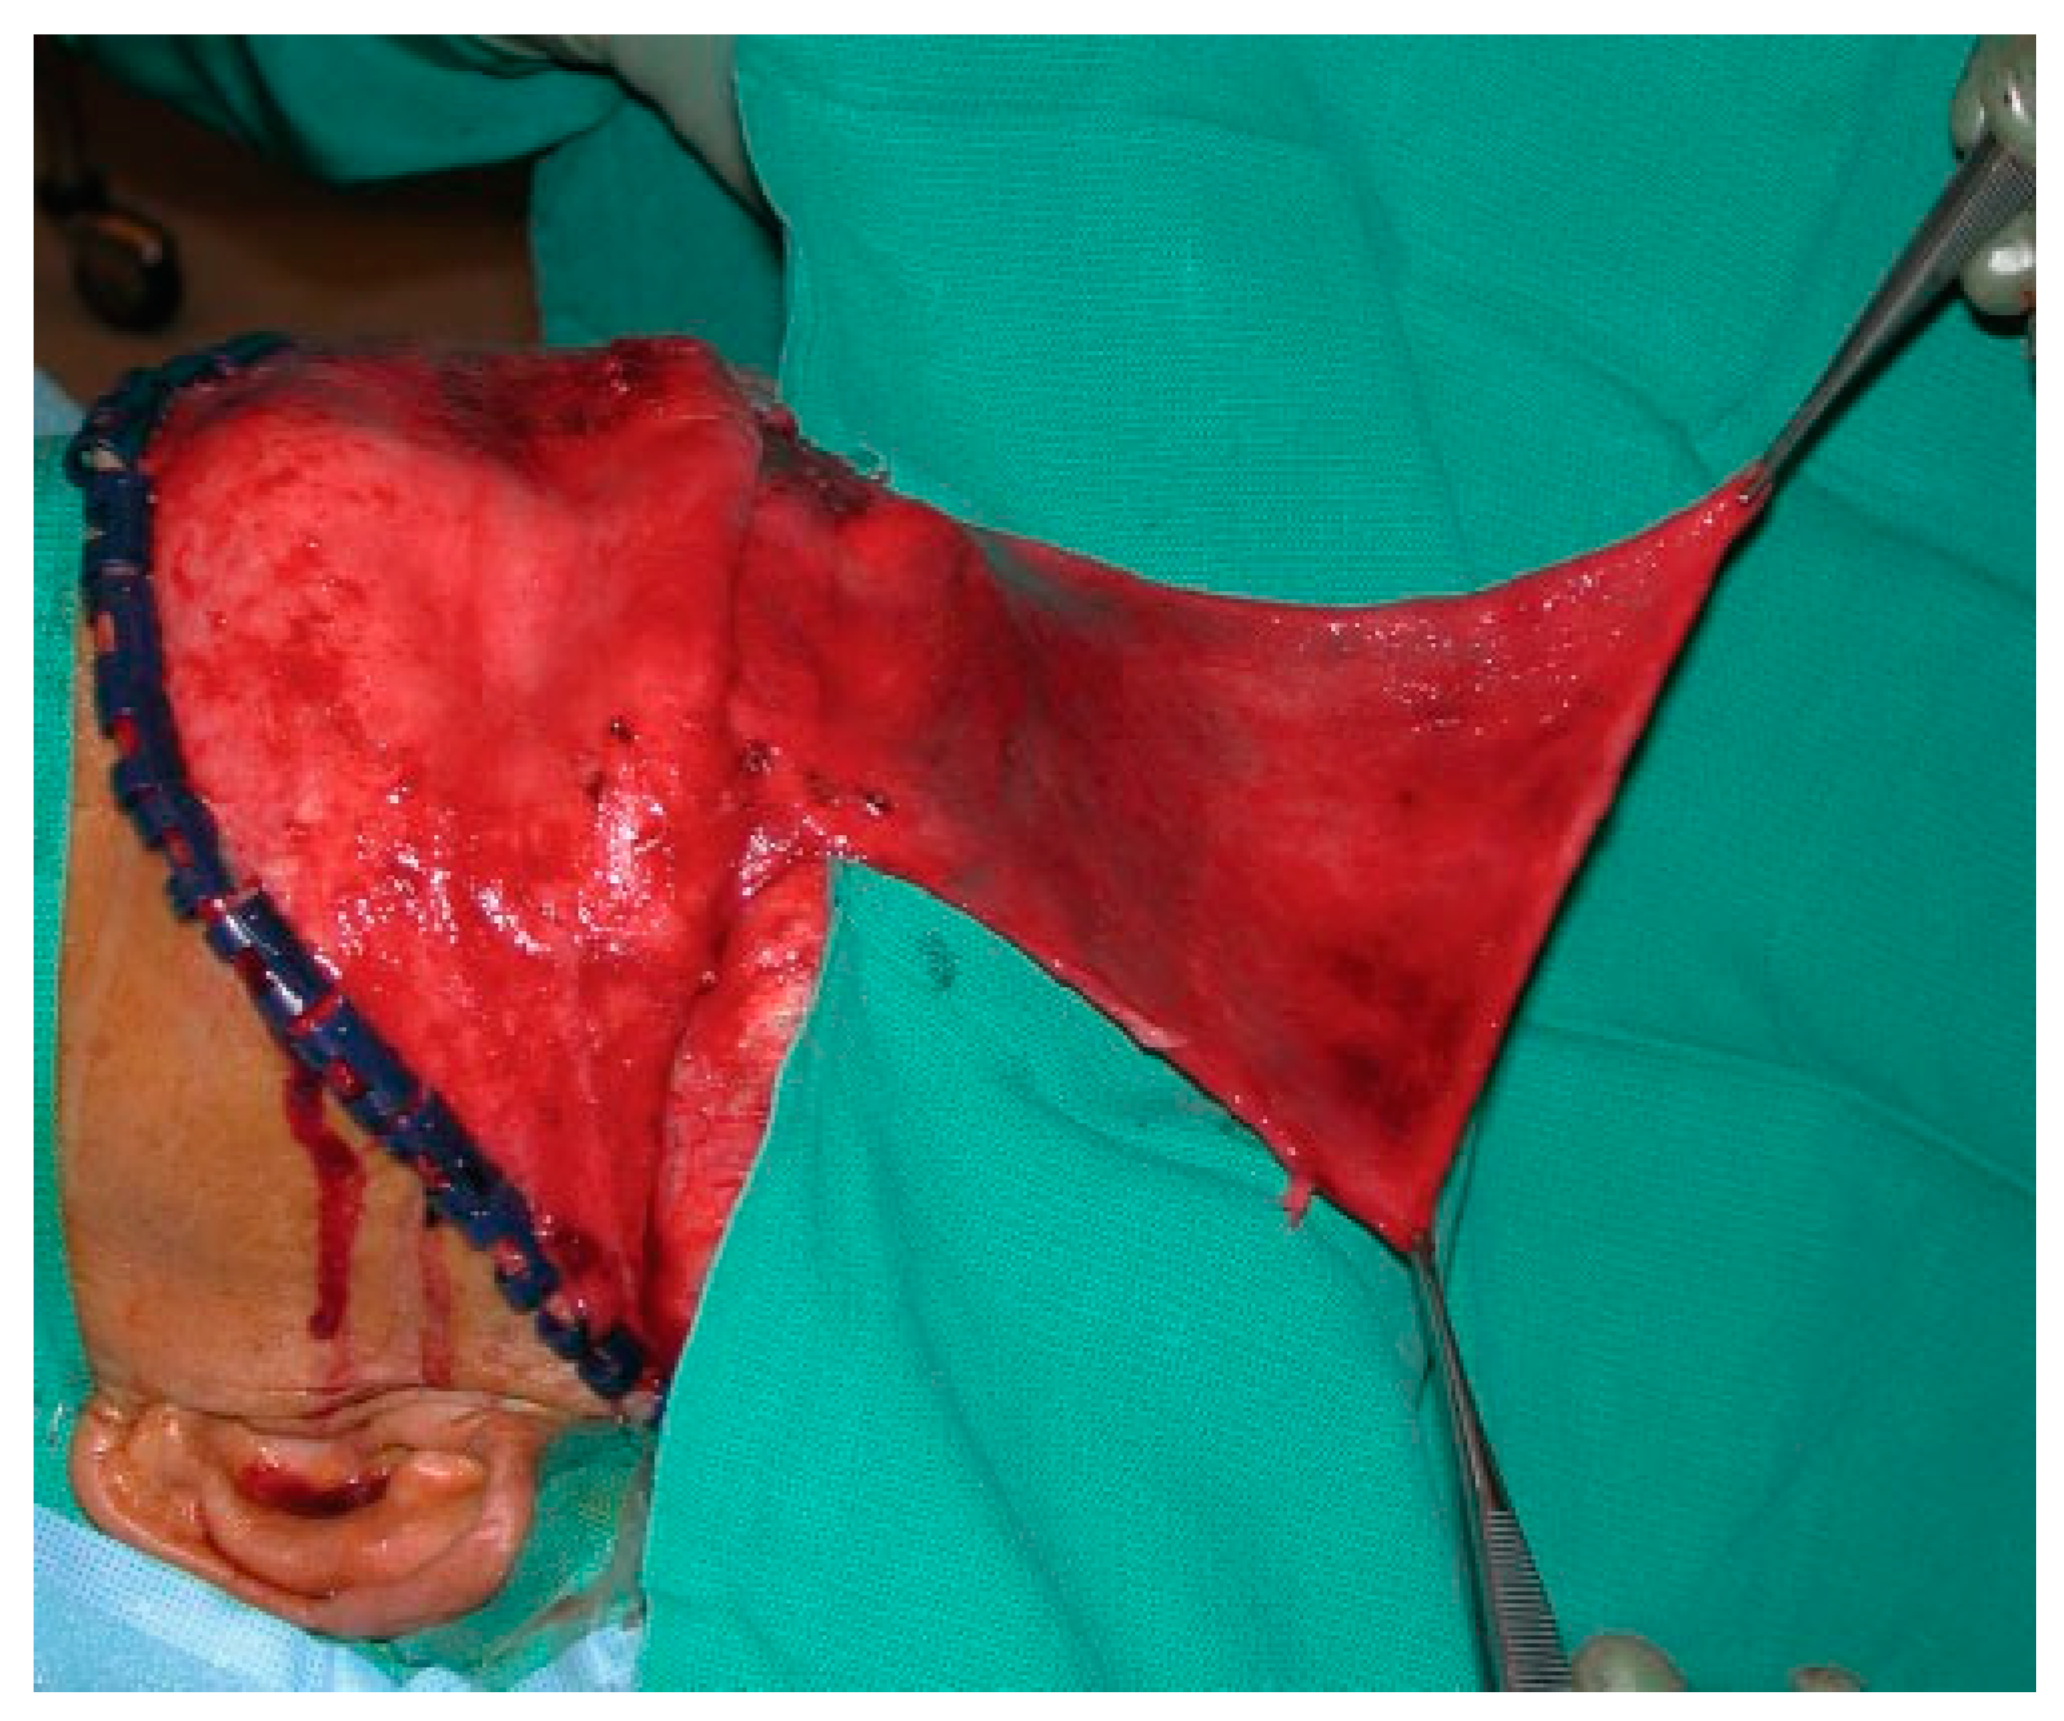

The scalp is then rotated forward, and blunt or sharp dissection can be used to elevate the subgaleal flap to a level 3 to 4 cm above the orbital rims. Care is taken to avoid injury to the supraorbital and supratrochlear neurovascular pedicles. The pericranial flap is then incised parallel and 2 cm behind the initial scalp incision. Two lateral incisions are placed 2 cm cephalad to the temporal line, which allows elevation of the pericranial flap over the orbital rims. Although periosteal lacerations may exist at the fracture site, a careful dissection will usually maintain an intact vascular supply and provide a lengthy flap that can be used for repair of unanticipated CSF leaks or obliteration of the sinus if it is small (Figure 16).

Figure 16.

Intraoperative photo of a large pericranial flap.